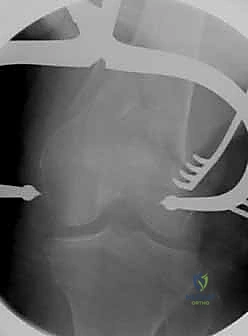

- الأشعة السينية (X-Rays): أخذ صور من زوايا متعددة (أمامي خلفي، وجانبي) لتحديد موقع الكسر ونوعه.

- الأشعة المقطعية (CT Scan): وهي ضرورية جداً في كسور عظم الفخذ البعيدة، خاصة إذا كان الكسر يمتد إلى داخل مفصل الركبة (Intra-articular fractures). تساعد الأشعة المقطعية الدكتور هطيف على بناء نموذج ثلاثي الأبعاد للكسر، مما يسهل التخطيط الجراحي وتحديد أماكن وضع المسامير بدقة.

قبل بدء الجراحة، يتم رسم خطة دقيقة. يتم وضع المريض على طاولة العمليات المجهزة بأشعة (C-Arm) لضمان التصوير الفوري أثناء الجراحة.